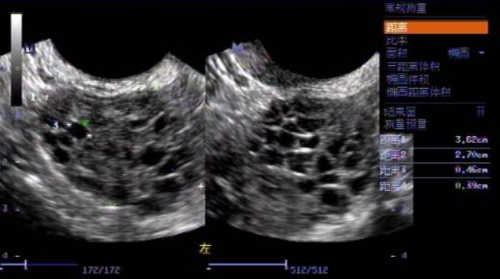

我与爱人结婚后,就开始积极的备孕要宝宝,但是要了有两年的时间,却一点声音也没有。于是就开始了我们的求医之路,曾经我们辗转了当地的多家医院。医生根据我的月经史和内分泌情况为我诊断为多囊卵巢综合症,还有糖脂代谢异常。这些都导致了精卵质量受到了影响。于是就在医院进行了多个周期的监测卵泡和诱D排卵以及指导同房,最终卵泡都是长不起来,即使偶尔会有1-2两次的正常排卵,但是受孕最终也都失败了。